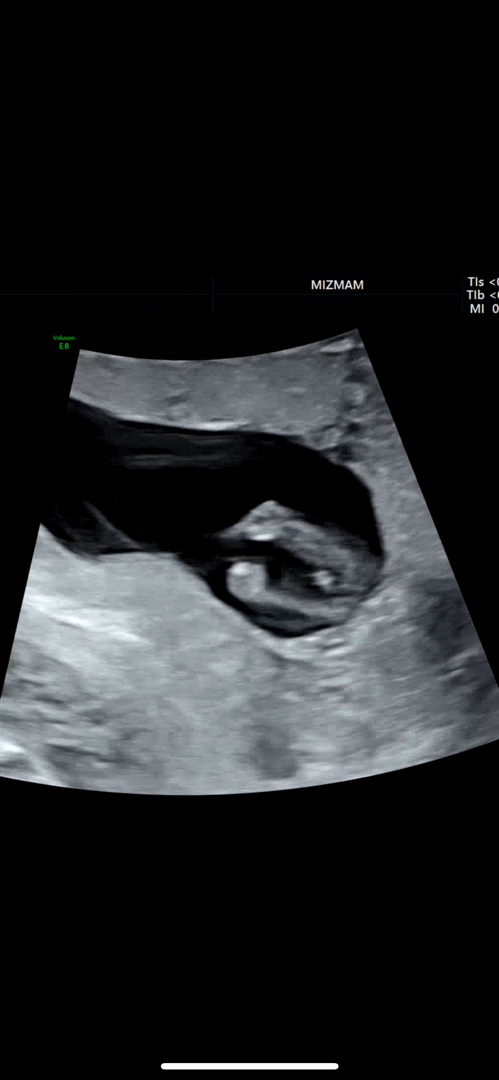

아들인것같나요? 12주4일

오늘 입체 초음파찍었는데 다리사이에 뭐가 보이는거같아요! 12주4일인데 아들일까요?

12주엔 남녀 모두 생식기가 돌출되어 있어서 다리 사이로는 성별 구분이 어려워요